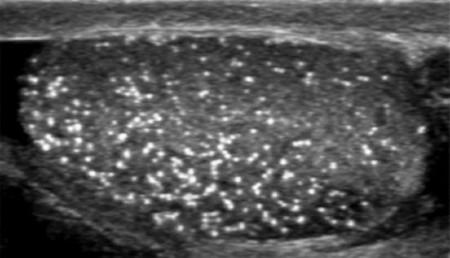

ΑΝΔΡΙΚΗ ΥΠΟΓΟΝΙΜΟΤΗΤΑ

Η ανδρική υπογονιμότητα αναφέρεται στην αδυναμία ενός ώριμου άνδρα να αποκτήσει παιδιά με μια γόνιμη γυναίκα. Η ανδρική υπογονιμότητα είναι υπεύθυνη για το 50% όλων των άτεκνων ζευγαριών.

Στο 30-40% των ανδρών που αδυνατούν να τεκνοποιήσουν, δεν εντοπίζεται κάποιο σαφές αίτιο (ιδιοπαθής ή ανεξήγητη υπογονιμότητα).